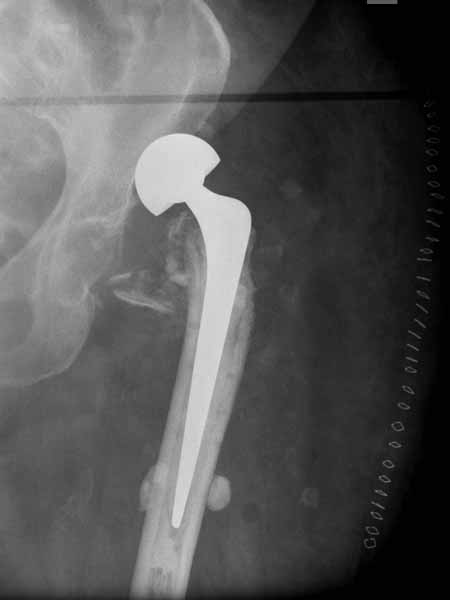

а куда делся фрагмент большого вертела? Очевидно,

Если среднеягодичная мышца не рефиксирована, то ничто не держит протез во впадине и это закономерный результат.